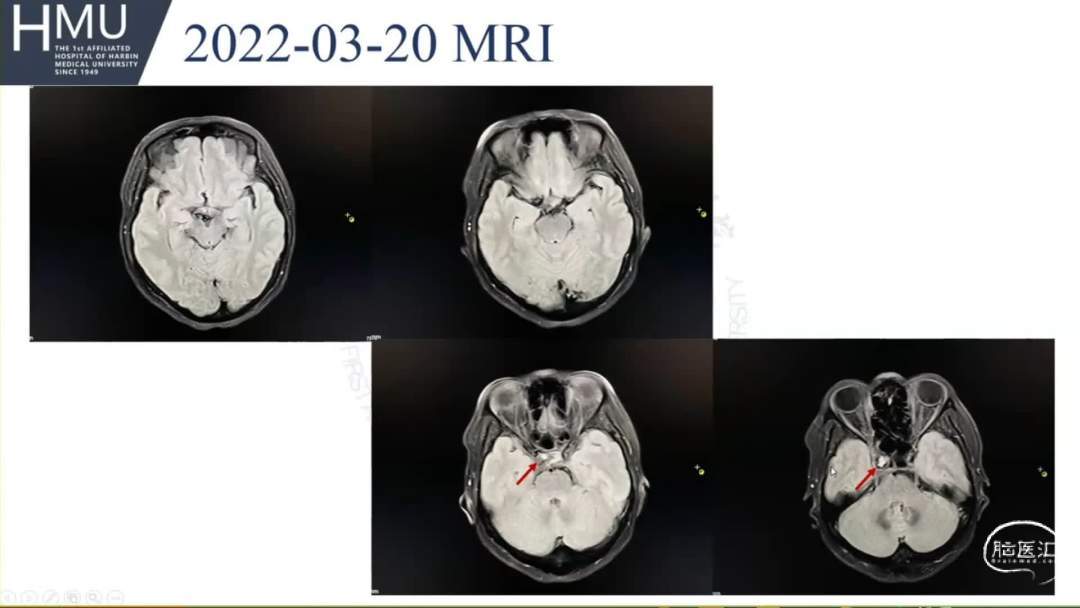

●女,52岁,因“头痛4日,右侧眼脸下垂1日” 入院

入院前4日无诱因出现后枕部头痛,呈针刺样持续性疼痛,入院前1日,出现右眼睑下垂伴眼球胀痛

神清语明,右眼球固定,双侧瞳孔

左:右=2.5mm:5mm,右眼光反射消失,颈强阳性。